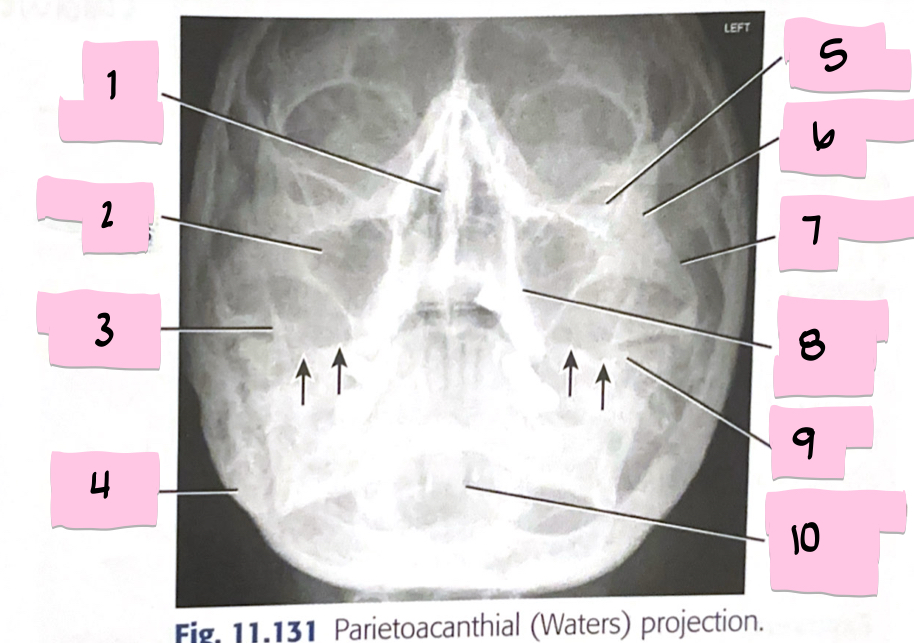

What is 1 pointing to?

Bony nasal septum

What is 2 pointing to?

Maxillary sinus

What is 3 pointing to?

Coronoid process

What is 4 pointing to?

Mastoid process

What is 5 pointing to?

Inferior orbital rim

What is 6 pointing to?

Zygomatic bone

What is 7 pointing to?

Zygomatic arch

What is 8 pointing to?

Maxillary alveolar process

What is 9 pointing to?

Petrous ridge

What is 10 pointing to?

Dens within foramen magnum